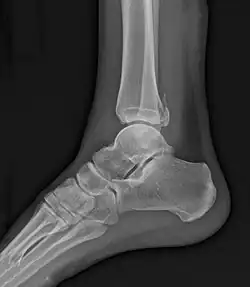

Fracture de Maisonneuve

La fracture de Maisonneuve comprend une rupture du ligament deltoïde ou une fracture-avulsion horizontale de la malléole interne, associée à une longue fracture oblique de la fibula (péroné).

La fracture est associée à une déchirure de la partie distale de la syndesmose tibio-fibulaire et de la membrane interosseuse avec parfois une lésion du nerf fibulaire (nerf péronier commun ou nerf sciatique poplité externe) qui passe au niveau du col de la fibula. Cette atteinte du nerf peut entraîner une paralysie de la loge musculaire antérieure de la jambe, d’où l'impossibilité de relever le pied.